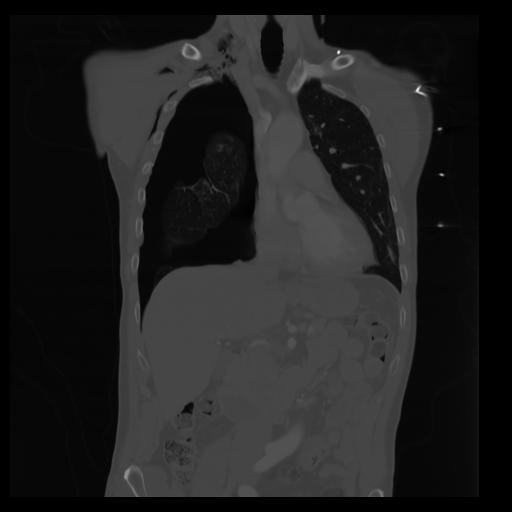

29 CUERPO,CE,Coronal,3.000,CUERPO,Coronal,